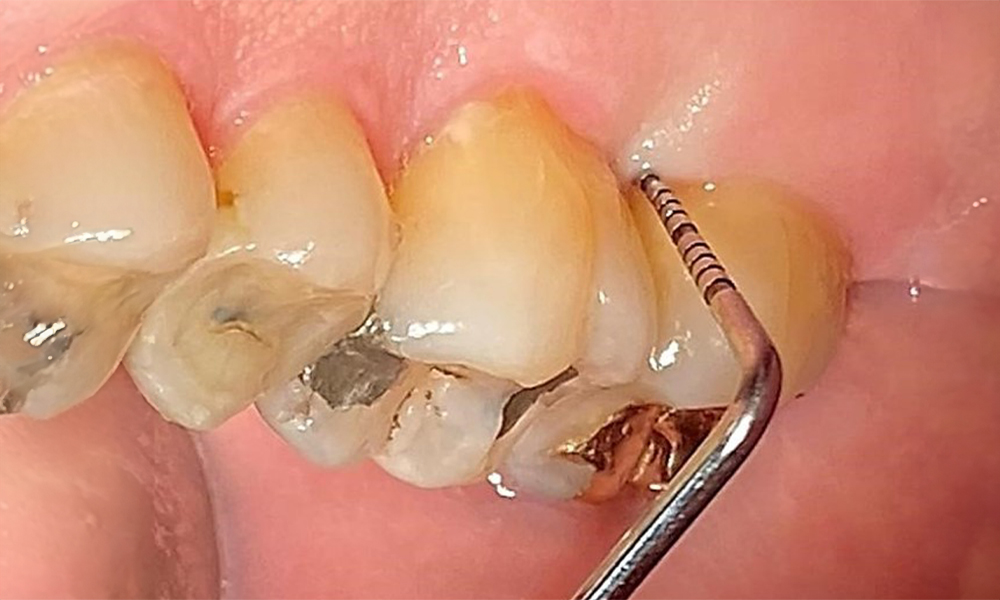

Supragingival and subgingival biofilm removal is indispensable for maintaining the stability of the periodontal condition. Air polishing using low-abrasive powder is suitable for this purpose. Periodontal pockets and exposed root surfaces must be cleaned with low-abrasion powders. The use of a flexible parotip is recommended for patients with increased probing depths (deeper than 5 mm) (Fig. 10). (9)

Subgingival application of the flexible air polisher tip (Proxeo Aura, W&H, shown here) to the mesiopalatal aspect of tooth 27 with a periodontal pocket depth of 5 mm.

Fig. 10: Subgingival application of the flexible air polisher tip (Proxeo Aura, W&H, shown here) to the mesiopalatal aspect of tooth 27 with a periodontal pocket depth of 5 mm. © Dr R. Krapf